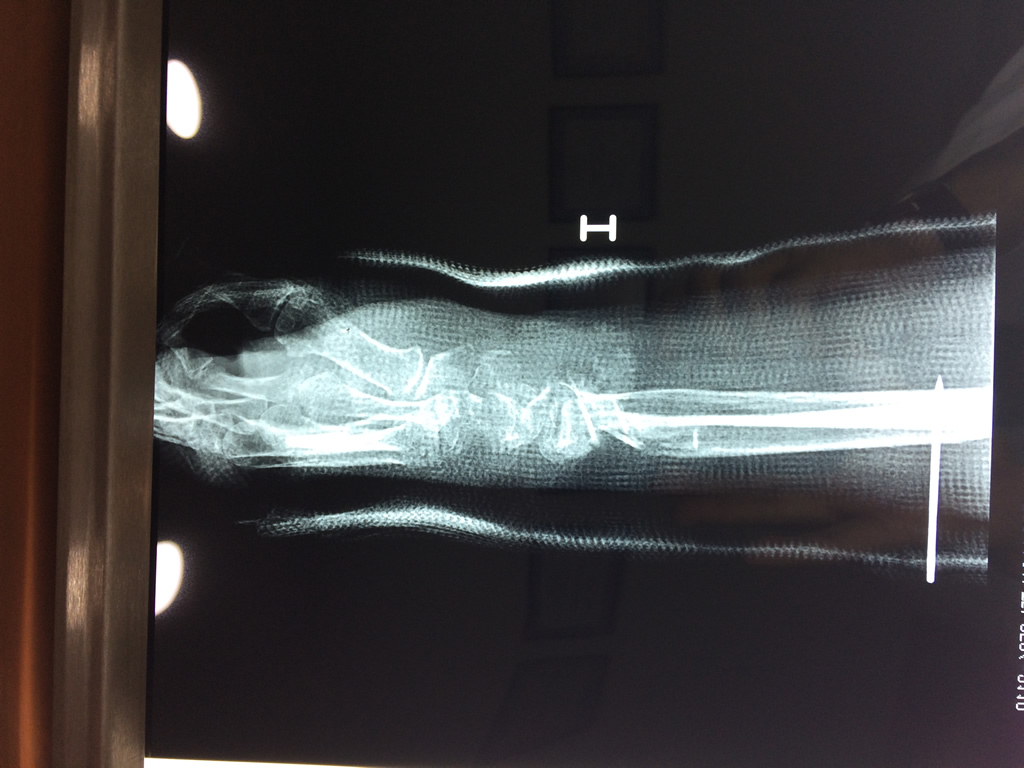

Cirugías de Muñecas

Los procedimientos más comunes en cirugía de la mano son aquellos destinados a reparar traumatismos, incluyendo lesiones de tendones, nervios, vasos sanguíneos, y articulaciones; huesos fracturados; y quemaduras, cortes, y otros daños de la piel.